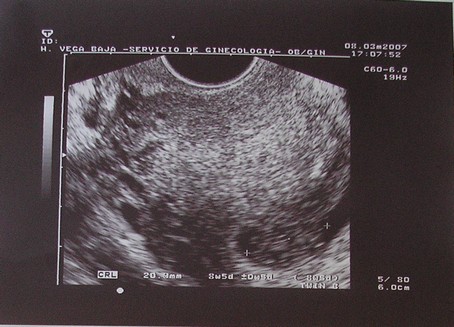

újra gratu és duplán